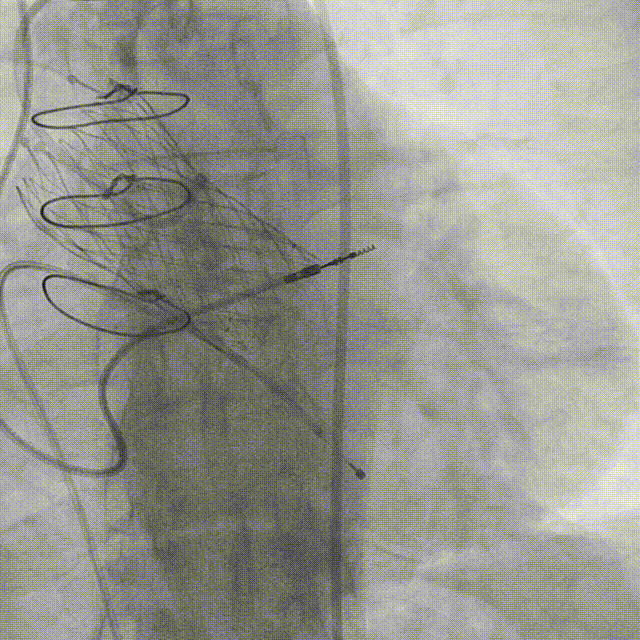

2012年植入26VenusA-Valve瓣膜植入后造影。

2.TAVR术后冠脉造影:

3.经左股动脉角度猪尾行主动脉根部造影。

4.猪尾直接跨瓣并进行左室测压。